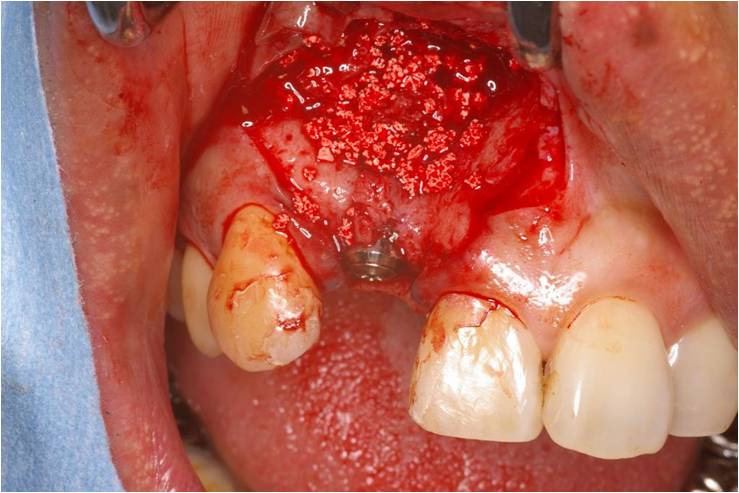

2011年7月10日 前歯部GBR症例

前歯が折れて来られた患者さんです。インプラントの周囲に十分な骨がなかったので、骨を作る為に人工骨を入れました。下写真 怖い人は見ないでください。